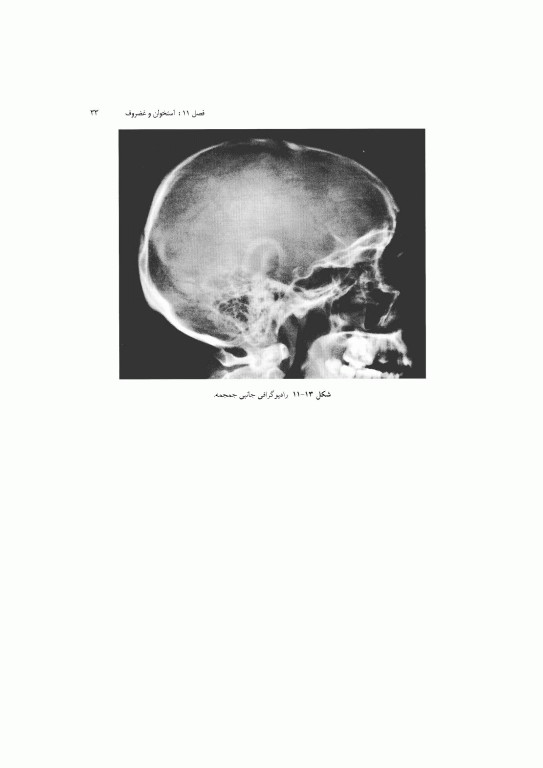

1. آناتومی بالینی: پایه این بخش اطلاعات پایه سودمندی را برای کمک به پزشک در تشخیص و طراحی درمان ارائه مینماید. نمونه‌های متعدد رادیو گرافهای نرمال، CT اسکن، MRI و سونوگرامهای مربوطه نیز نشان داده شده است. همچنین، تصاویری از آناتومی مقطع عرضی آورده شده است تا دانشجو با تجسم آناتومی سه بعدی آشنا شود که این امر در تفسیر کلیشه‌ها بسیار مهم است.